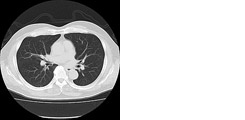

胸腹部CT検査:17,600円(胸部・腹部それぞれ単独での撮影も可能です)

胸部CTは肺疾患(肺がん・肺気腫など)の検索にお勧めします。 喫煙されている方は特にお勧めします。腹部CTは肝・胆・膵・腎・脾臓の異常の早期発見に有効です。